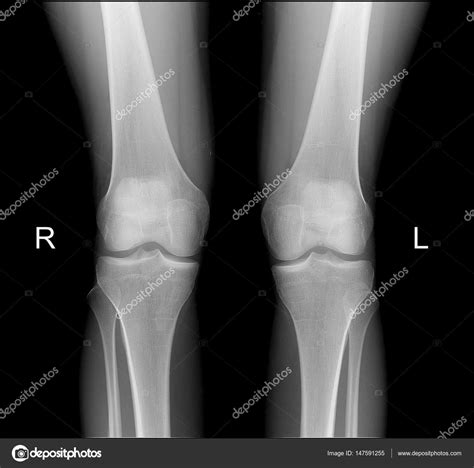

Healthy Knee Xrays

Interpreting Healthy Knee X-rays

Interpreting knee X-rays requires a trained eye. Here are some key features that radiologists look for in Healthy Knee X-rays:

• Bone Structure: The bones of the knee, including the femur, tibia, and patella, should appear smooth and intact without any fractures or deformities.

• Joint Space: The space between the bones should be uniform and not narrowed, which can indicate wear and tear or arthritis.

• Soft Tissue: While X-rays primarily show bone, the soft tissue around the knee should appear normal without any signs of swelling or inflammation.

• Alignment: The knee joint should be properly aligned, with no signs of dislocation or misalignment.

• normal healthy knee x rays

• normal knee x rays female